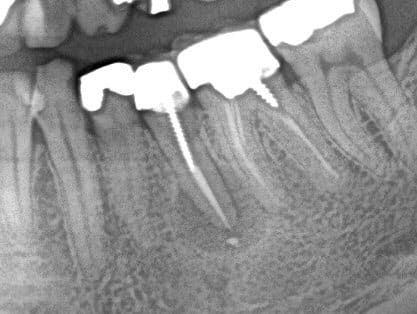

Voici la radio post op d'hier.

J'ai obturé a l'arrache avec mta fluide au debut pour tapisser les parois (light) puis compact ensuite pour faire la solidite de l'obturation (effet putty) foulé avec mini fouloir amalgame+boulette de coton seche pour retirer exces humidité et polir.

On verra pour la cicatrisation ce que ca donnera.

l'endo avait l'air plutôt propre. bizarre.

t'as pu isoler ton site opératoire ?

Parce que ce qu'il reste de la couronne clinique a l'air réduit à peau de chagrin.

- en ce qui concerne le cas je suis assez intrigué par la disparition du liseré de condensation osseuse à la marge de la lésion initiale, sur la radio post-op. Cela appelle une question de chronologie: la radio initiale est prise combien de temps après le traitement endodontique orthograde? et la post-op combien après la chirurgie?

Parce que vu d'ici, le réseau de trabéculations net dans la zone apicale fait penser à une rémission en cours confirmée par la disparition de la densification osseuse au pourtour de la lésion apicale sur la radio post-op. En d'autres termes je me demande s'il n'y a pas eu précipitation à ré-intervenir.

La radio preop est un recadrage de panoramique effectuee 2 semaines avant la post op.

Ce qui a motivé: Abces carabiné sur la racine.

Apres decollement du lambeau il y avait une fenestration corticale apicale.